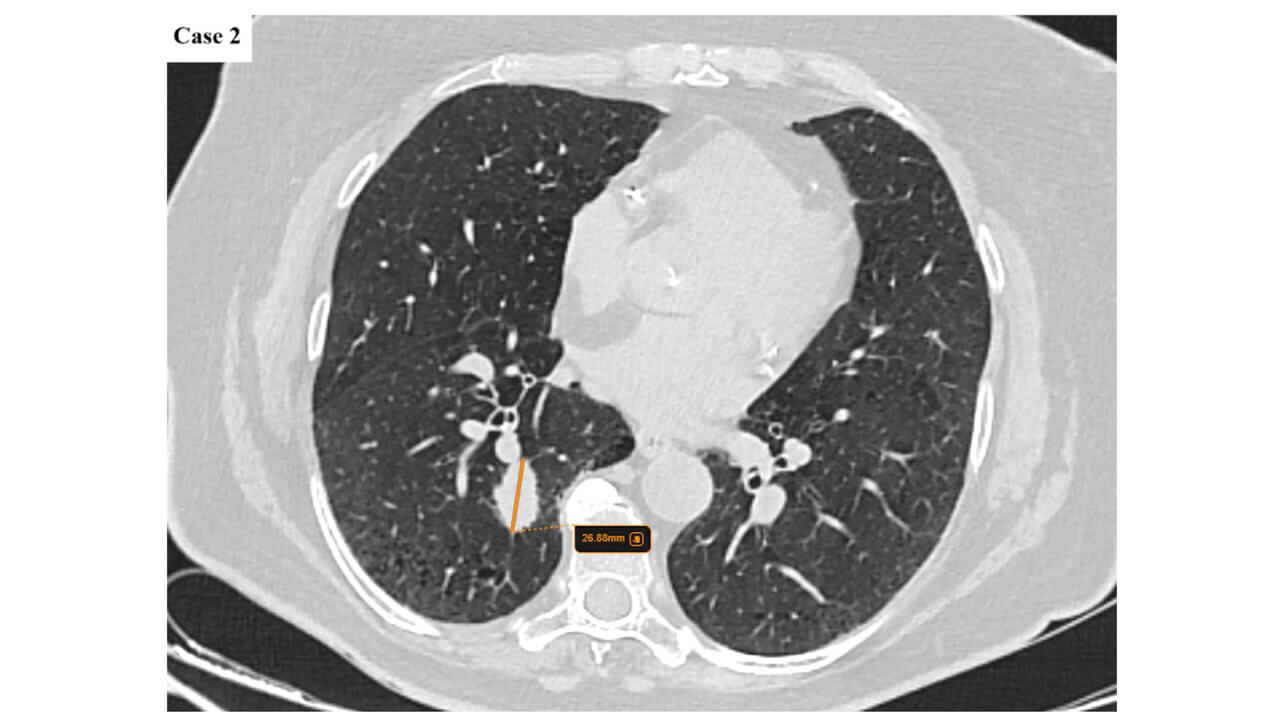

- CT (computed tomography) of the chest and abdomen – assessment of tumor size and regional spread.

- PET-CT (positron emission tomography CT) – detection of metabolically active foci and possible distant metastases.